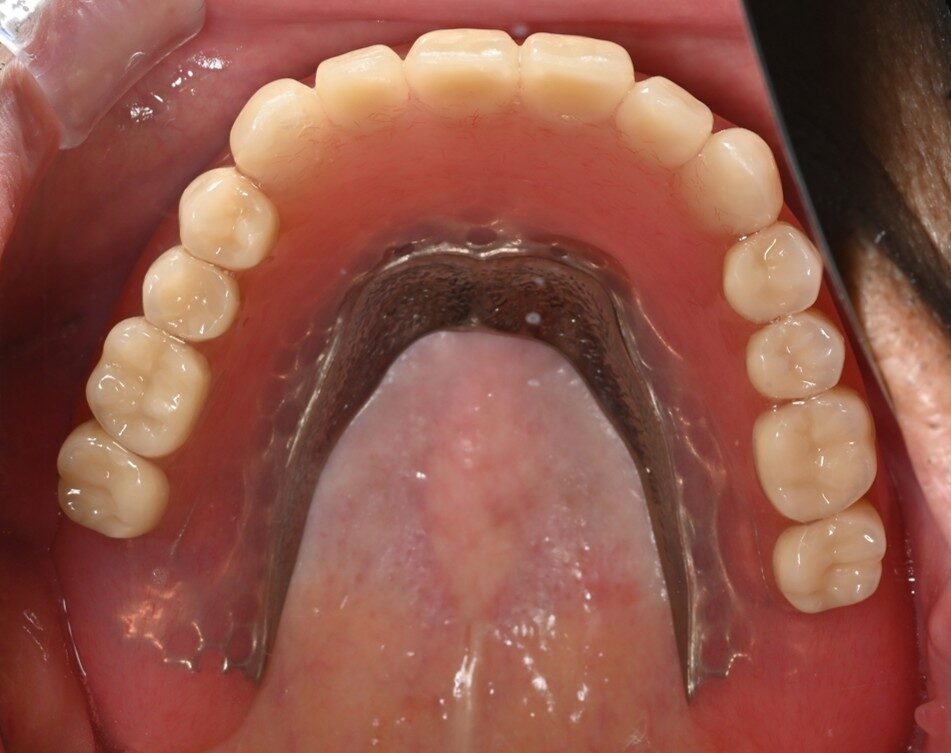

インプラント症例3

治療前

治療中

治療後

| 年齢・性別 | 70代 男性 |

|---|---|

| 主訴 | 「上の入れ歯が合わない。新しくしたい。」 |

| 治療内容 |

無口蓋義歯希望のためインプラントを4本埋入。 |

| 治療期間 | 5か月・10回 |

| 治療費用 | 総額:2,090,000円(税込) 【内容】上顎インプラントオーバーデンチャー 1,800,000円 ソケットリフト2本 5,0000円×2=100,000円 |

| リスク・副作用 | ・外科処置が必要。 ・自費診療(保険適用外)となる。 ・インプラント埋入後、旧義歯がゆるくなる可能性がある。 ・ソケットリフト後、稀に上顎洞内感染の可能性がある。 |